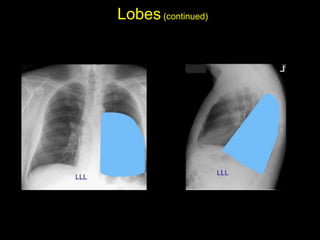

The document discusses the anatomy of the chest x-ray and CT scan by describing the lobes of the lungs and their locations. It also mentions the heart, mediastinum, hilum, and ribs. Several axial, coronal, and sagittal CT images are included with labels pointing out structures like the trachea, bronchi, lobes of the lungs, and fissures. In summary, the document provides an overview of lung and chest anatomy as seen on x-rays and CT scans through text descriptions and labeled medical images.